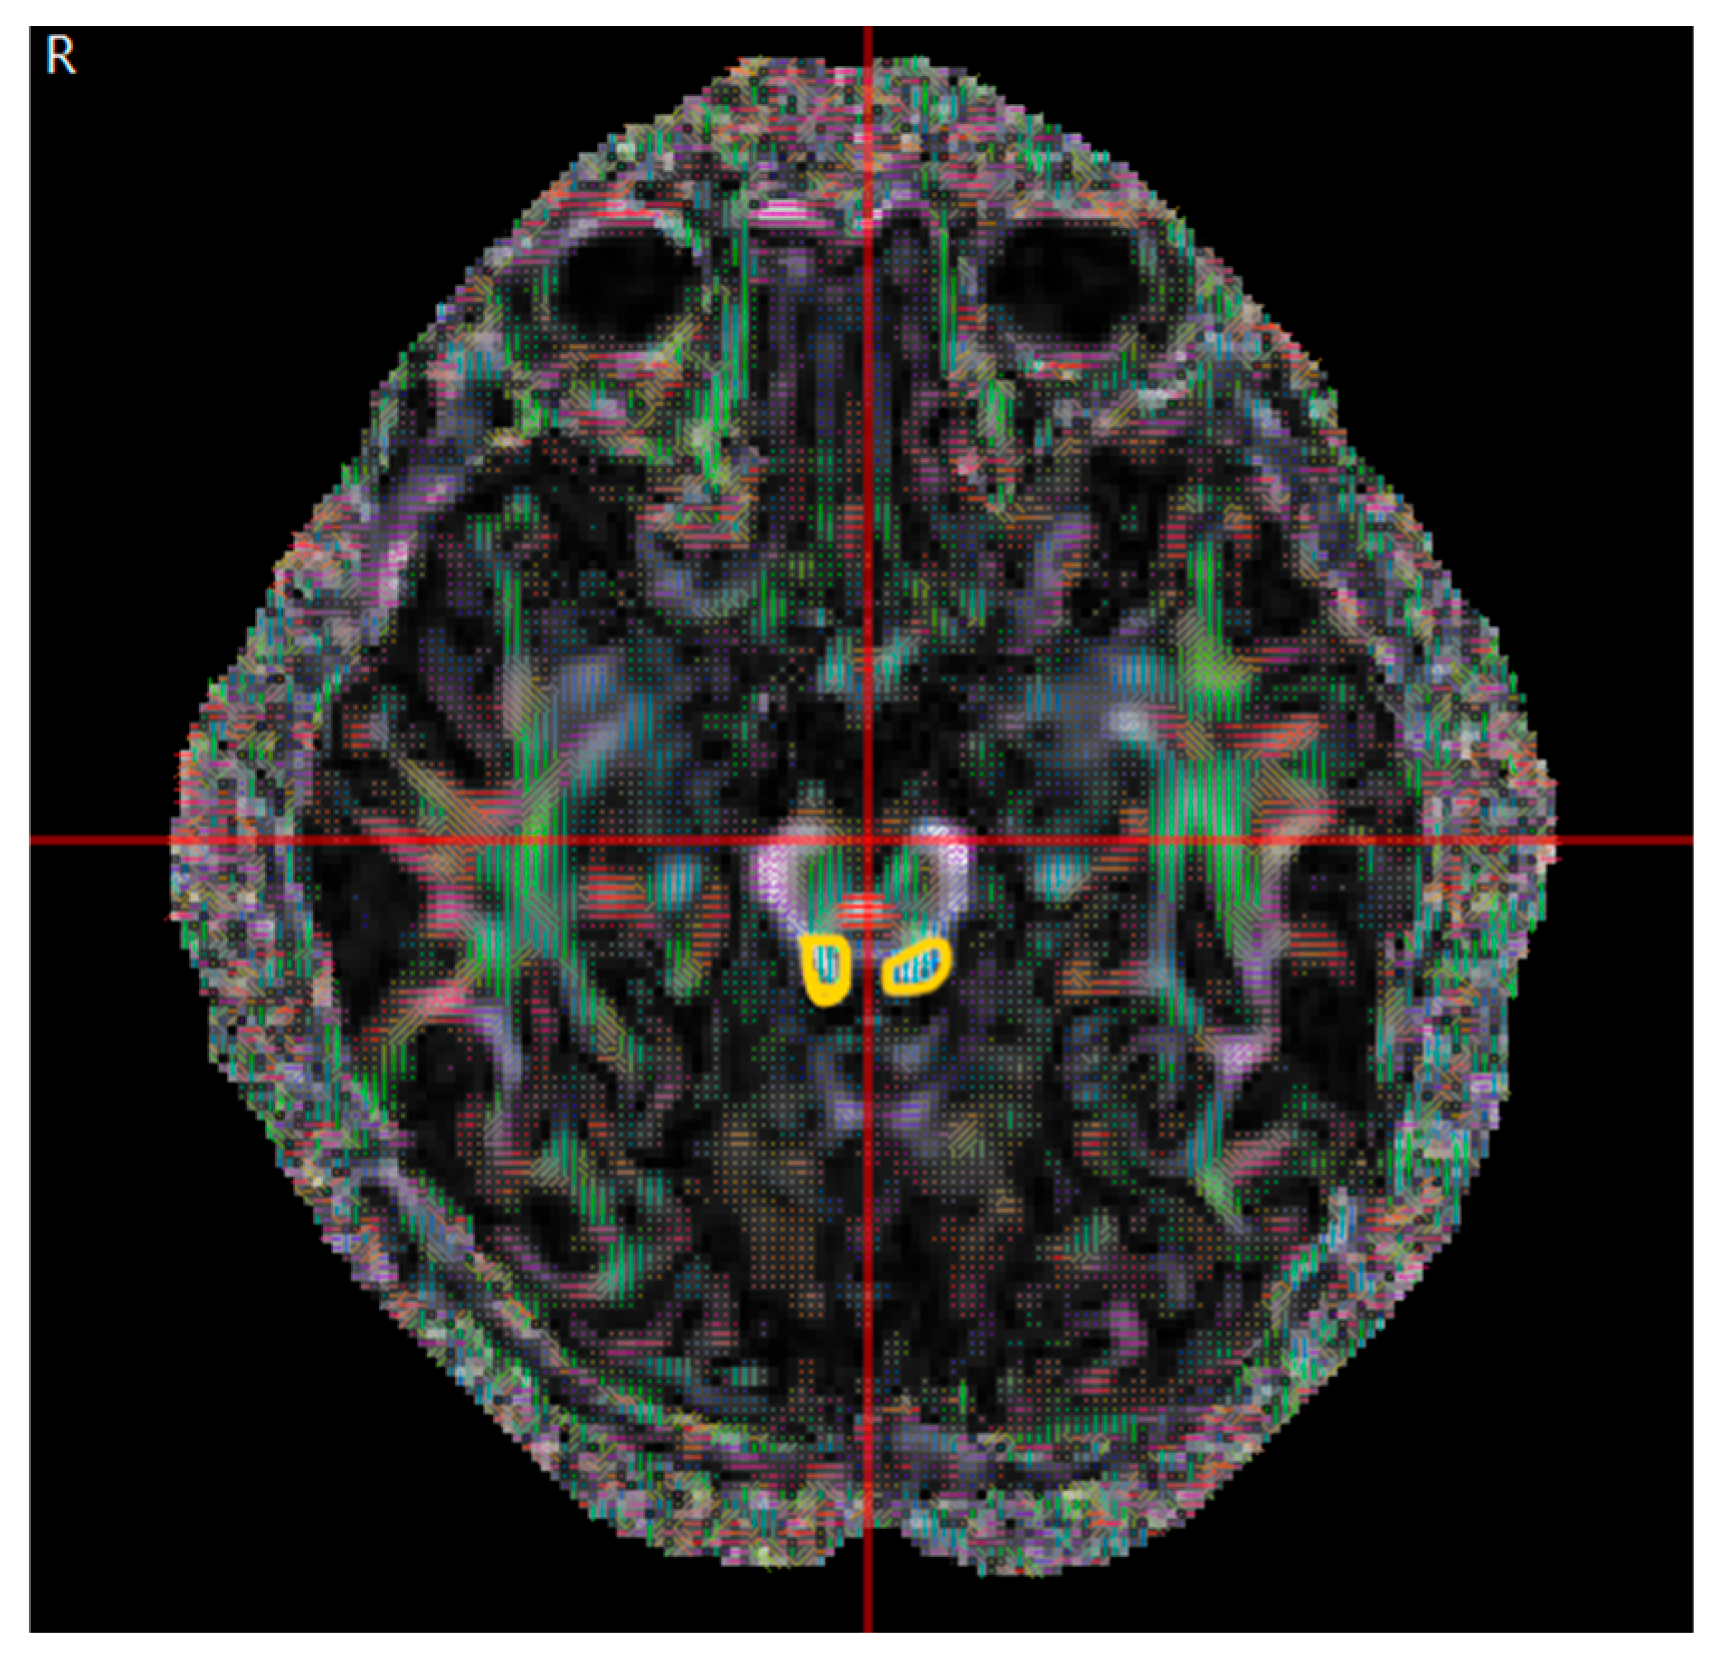

2.2. Data Collection

2.3. Basic Theory of DTI Metrics

2.4. Data Analysis